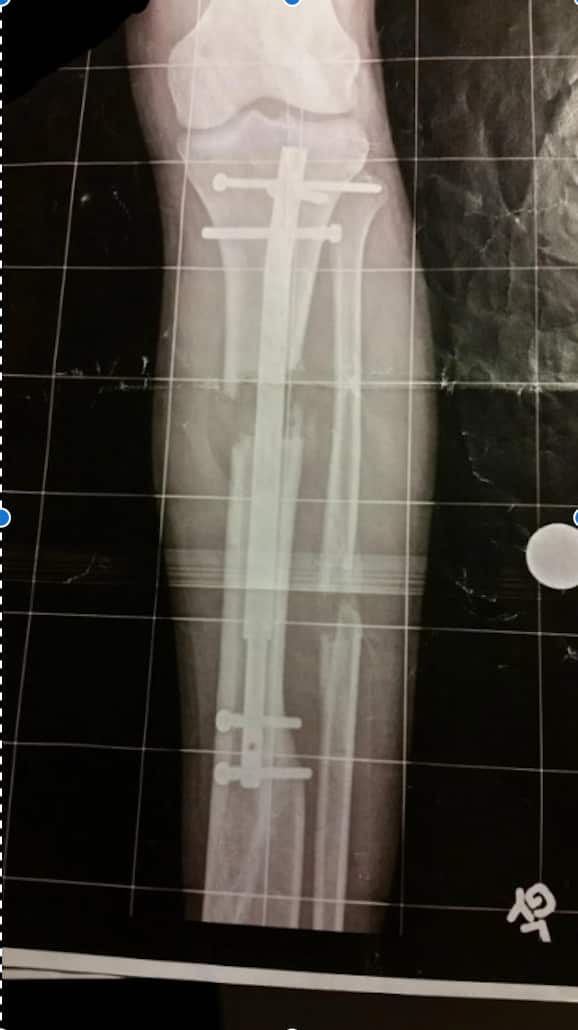

An X-ray of Victor Egonu's leg, three weeks into his lengthening procedure using an internal lengthening nail. Source: Supplied

- The Internal Lengthening Nail (ILN) method implants a telescoping rod inside the bone, lengthened by a magnet remotely, so there are no external hardware or scars. This means the procedure is more comfortable, but it costs more and requires precise surgery.

However, all methods are complex, lengthy and painful, with the patient requiring months of daily rehabilitation.